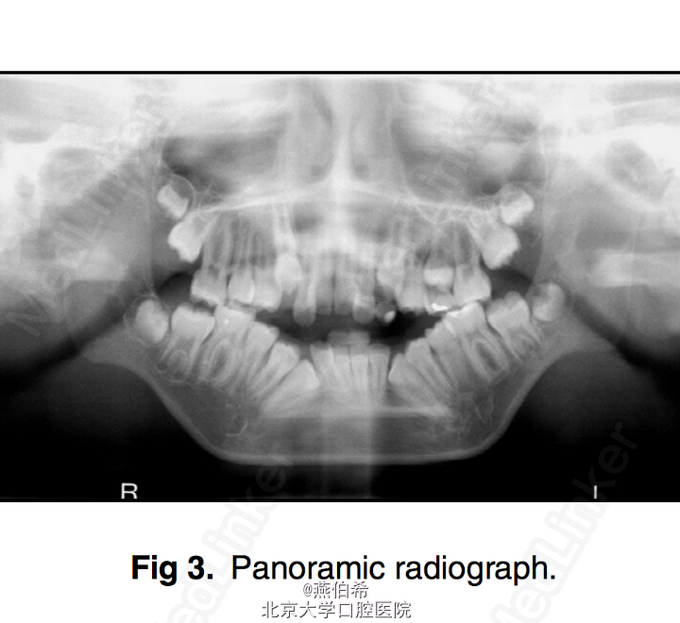

11岁非洲裔男孩,主诉牙不齐。 在New York-Presbyterian Morgan Stanley Children's Hospital (US news 儿科专业全美第9)接受颅面治疗,确诊为Treacher Collins综合征 婴儿时曾行气道造口,后右耳曾行鼓膜造口和置管以及左耳成型术

突面型,嘴唇无法闭合,口内10mm前牙开牙合,右侧3类磨牙关系,左侧1类磨牙关系。 头侧片显示极高角

Treacher Collins综合征 扩弓解决宽度不调,拔4个4矫正牙量骨量不调, 后行口外反L行截骨术矫正颌骨问题